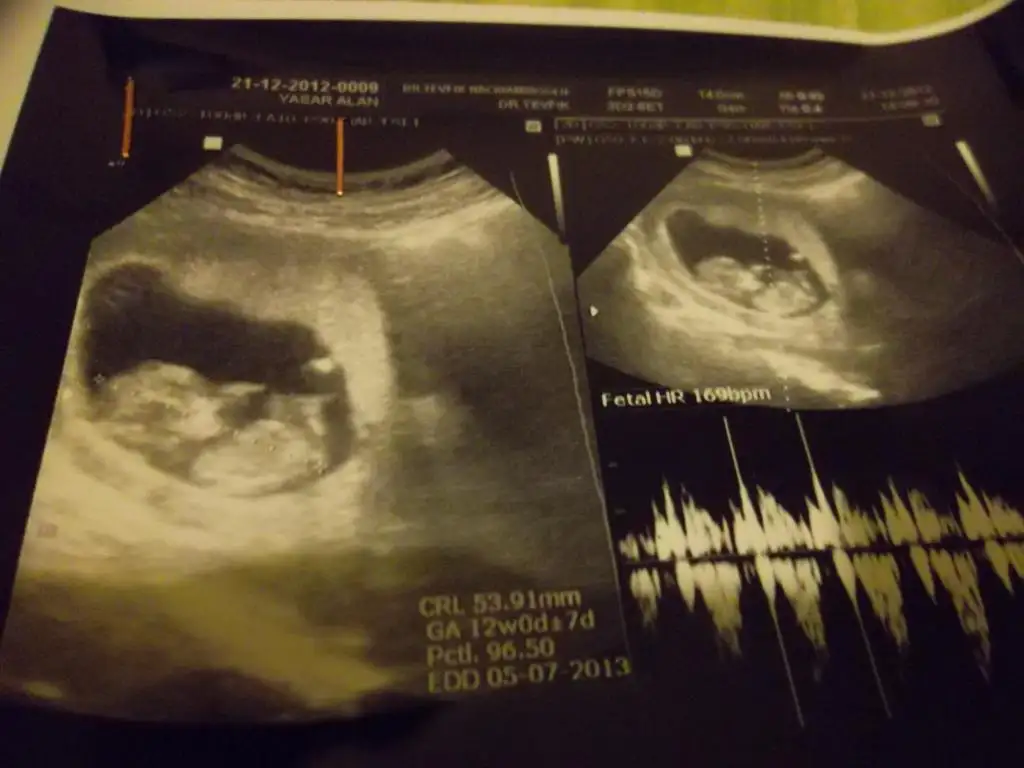

dr soylemeden siz gorun genital nub teorisi ( bebegin cinsiyeti)

kızlar bu da benimkinin son resmi :)) doktor erkek olabilir belki dedi orası çok karışık ama net bişey söyleyemem dedi bide siz bakın bakalım benim de içime hep kız doğuyordu çini rusu musu hepsinde de kız çıkıyordu bilemedim bende şimdi :))

kızlar doktor erkeğe benzetiyorum dedi ama nub bana paralel geldi sanki :44::44:

aslinda resmin tahmin icin uygun degil popsu asagida olmali tahmin icin ama bana cok parallel geldi, eger 13 haftada gittiysen bu nub kiz nubu:) ama onceden gittiysen aci degisebilir sonradan.

pardon alinti yapinca resmini daha net gordum aksine yukari dogru aci var sanki ama iste pozisyonu yanlis, pozisyona gore nubun gorunusu degisiyor.